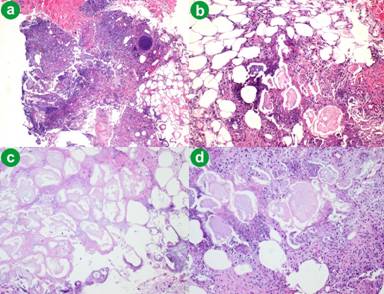

Dermatologic exam at that time revealed several scattered, tender erythematous subcutaneous nodules in bilateral lower extremities without ulceration. A punch biopsy of the lesions was performed which showed lobular panniculitis with prominent fat saponification and calcification necrosis. Scattered neutrophils and eosinophil’s were noted amongst the infiltrate (Figure 3).

Figure 3. a. 4x magnification showing lobular panniculitis. b. 10x magnification. c. Fat saponification and calcification necrosis. d. Necrotic adipocytes “ghost cells”. |

PP is usually confirmed with a subcutaneous biopsy and if the characteristic features of this entity are identified earlier on, an invasive biopsy could be averted [14]. The main histopathologic feature is a mostly lobular panniculitis without vasculitis. But, in the very early stage, a septal pattern has been described, which results from enzymatic damage of the endothelial septa, allowing pancreatic enzymes to cross from blood to fat lobules resulting in coagulative necrosis of the adipocytes, which leads to pathognomonic "ghost cells" (enucleated necrotic cells that have a thick wall with a fine basophilic granular material within their cytoplasm from dystrophic calcification) [15].